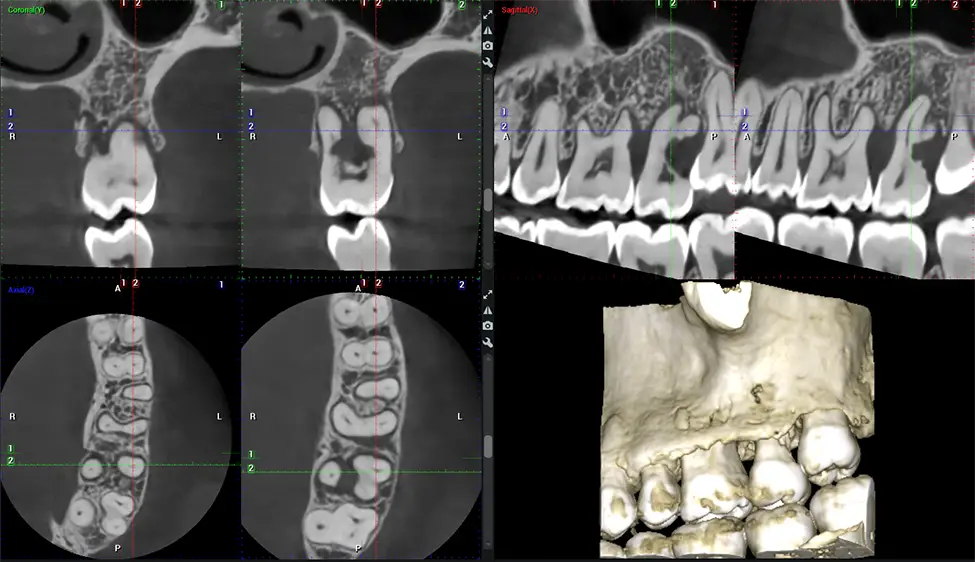

This 3D scan, called cone beam computed tomography, gives your dentist a more complete image of your oral anatomy and disease processes than a traditional X-ray. Unlike conventional X-rays, which capture a 2D image of your mouth from various angles, a 3D scan takes multiple digital X-rays for one image. It provides a complete view of your jaw, teeth, nerves, and soft tissues. This enhanced view allows dentists to detect minor issues not visible in traditional 2D scans, such as impacted wisdom teeth or bone fractures in the sinus cavity.

There are many benefits to using CBCT technology, especially compared to the traditional 2D X-ray format. One of the most significant advantages of CBCT scans is that they provide much more information than traditional X-rays. A scan lets your dentist see images from all angles of your jaw and mouth, including your sinuses, nasal cavity, cheekbones, and other surrounding areas. This added information helps your dentist craft a comprehensive treatment plan that addresses all aspects of your oral health.

Another significant benefit is that 3D imaging provides more precise images of your bone structure. These images are more detailed, providing you with a more accurate diagnosis. An accurate diagnosis means better treatment for you.

Our patented SCARA technology enables doctors to capture True Extraoral Bitewings that are as accurate at detecting caries as a 2D bitewing series, but with half the radiation dose. With our bitewings, doctors can view the apices of teeth on both jaws providing a more comprehensive view of the patients’ anatomy.